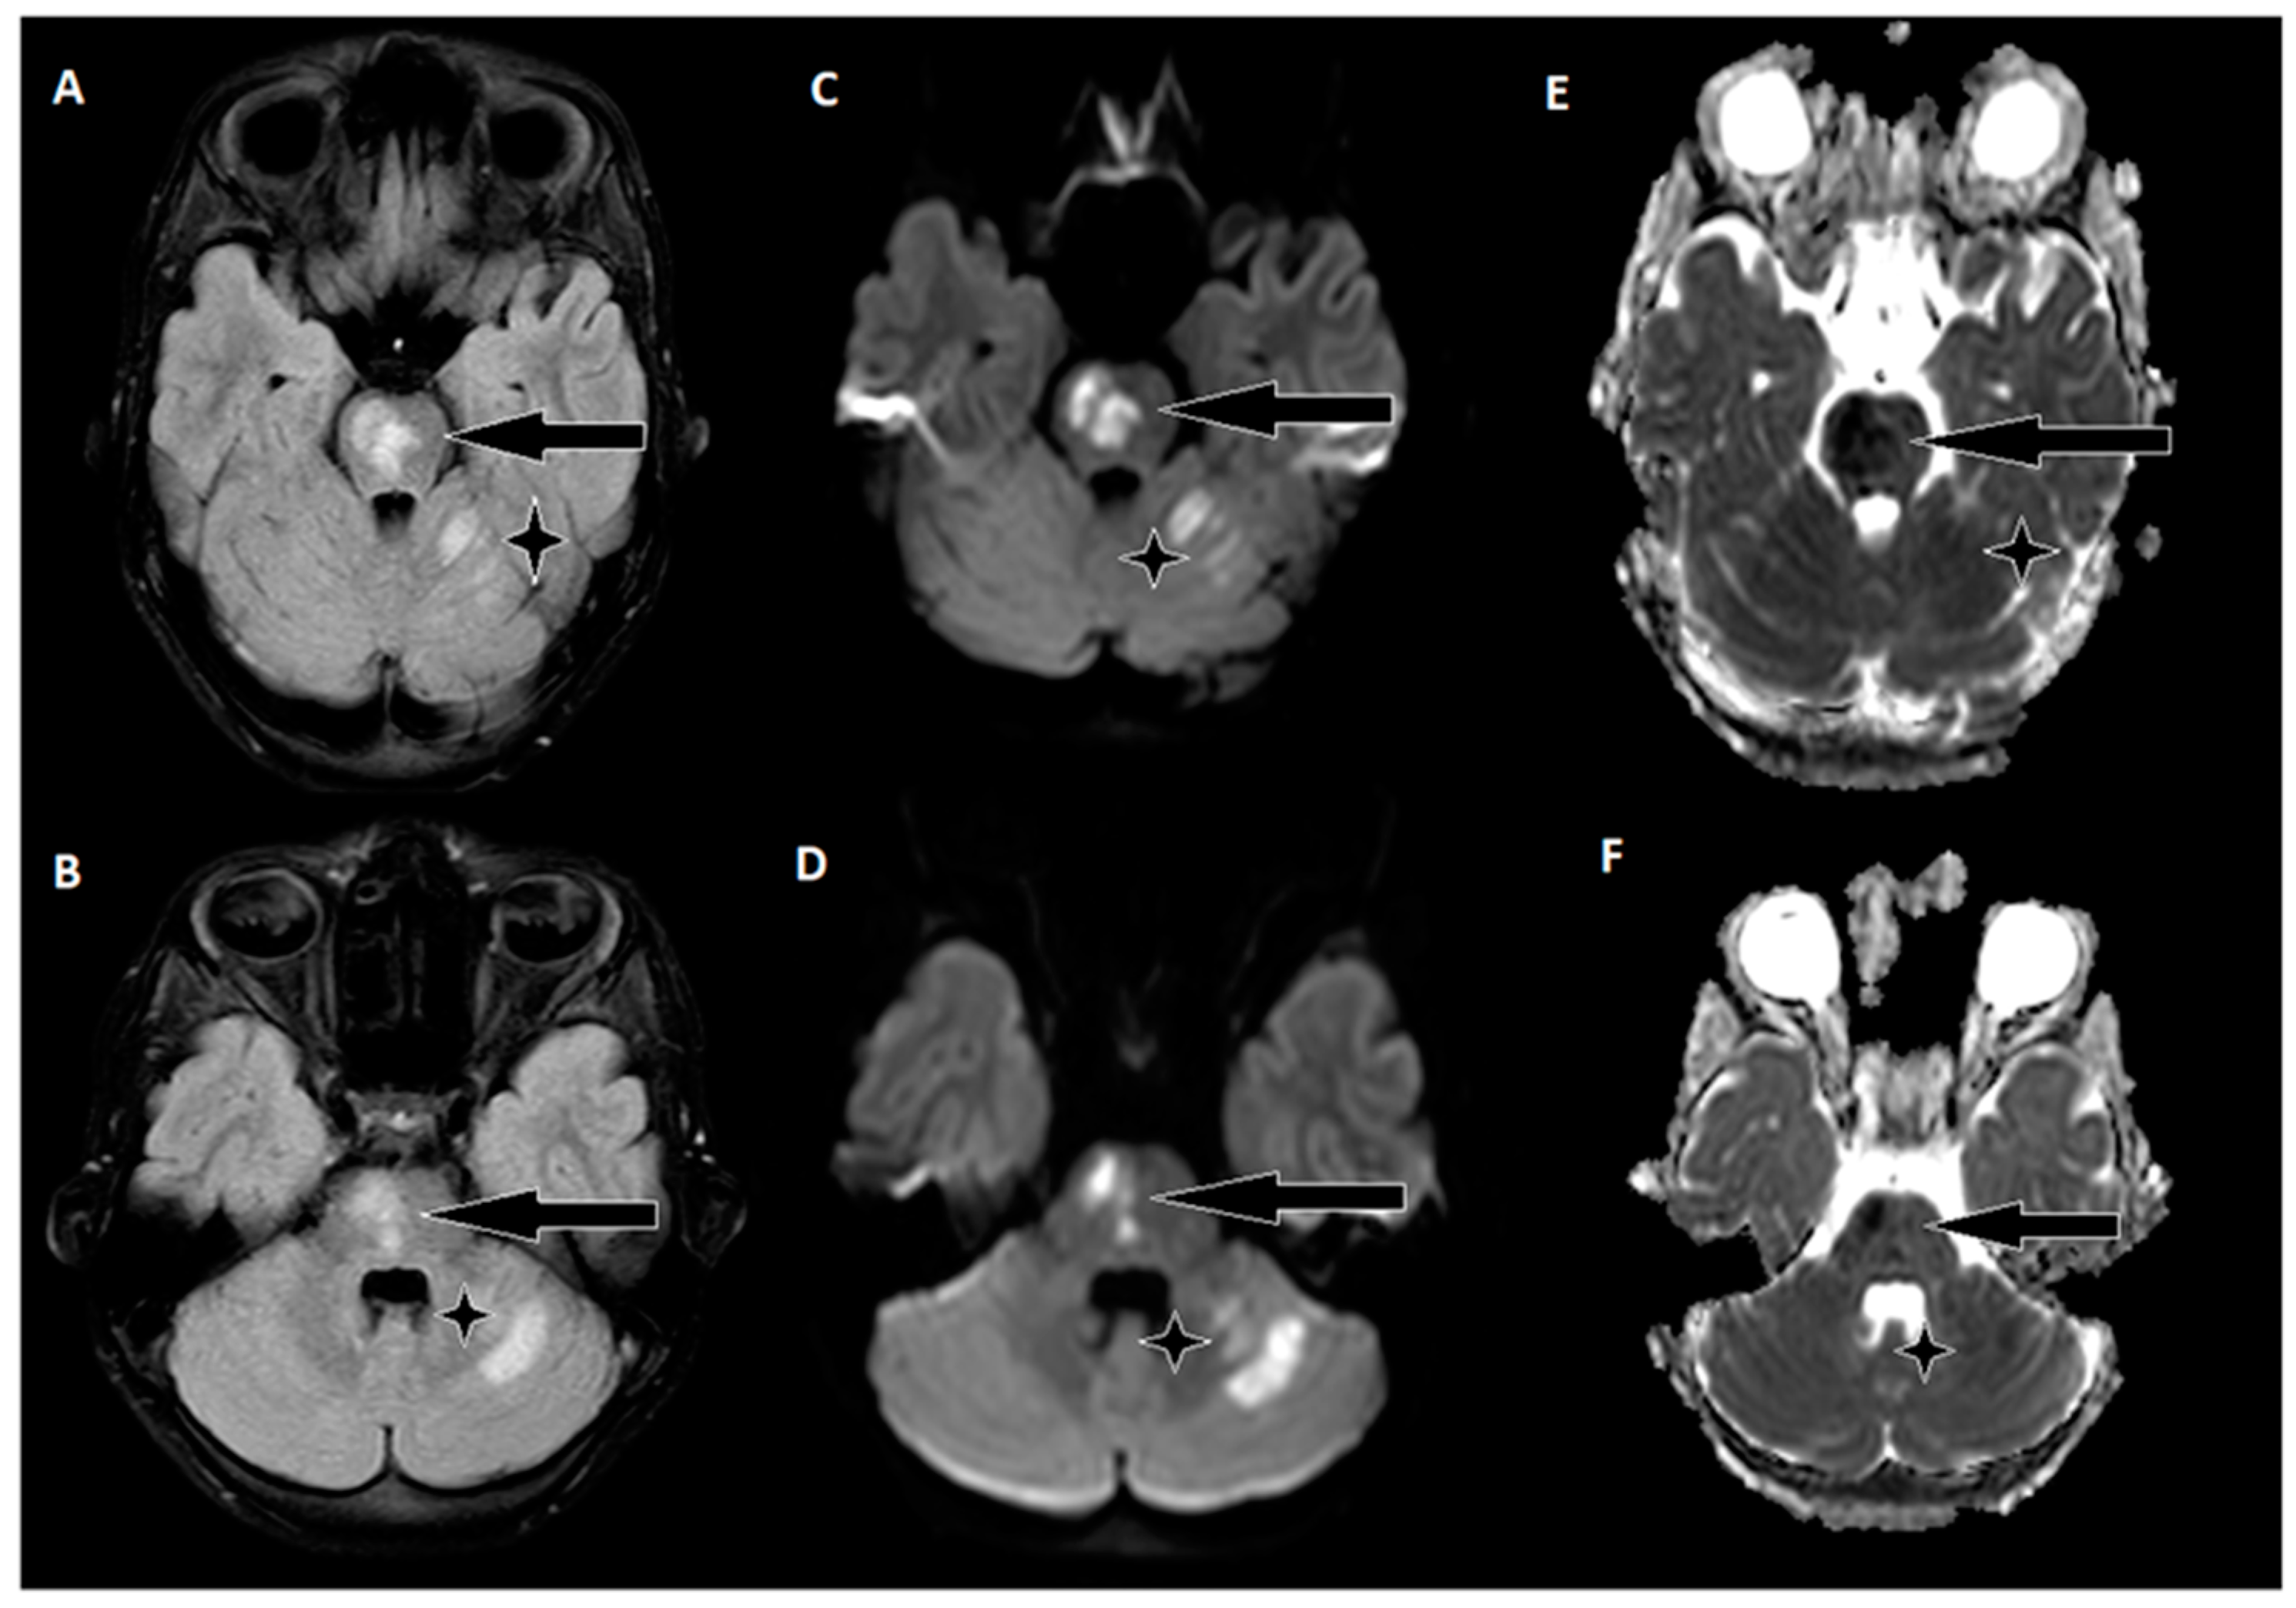

The day following EVT, an MRI of the brain was conducted (Figure 4), revealing hyperintense regions on the right side of the pons and the upper left cerebellum. Importantly, there were no indications of hemorrhagic imbibition, which was reassuring. In terms of treatment, the patient commenced a secondary stroke prevention regimen, consisting of Acetylsalicylic Acid at a daily dose of 75 mg. Additionally, low-weight molecular heparin 30 mg was initiated, administered twice daily to further mitigate the risk of complications. Just one day after the EVT procedure, the patient embarked on early rehabilitation, overseen by a team of physiotherapists and occupational therapists. Remarkably, the post-procedure period progressed without any significant complications, and the patient was transferred back to the Children’s Clinical University Hospital for continued evaluation and rehabilitation. At the time of transfer, the patient’s neurological status was characterized by plegia in the left arm and severe paresis in the left leg, with the latter exhibiting no voluntary effort against gravity. The patient’s GCS score was recorded as 14, and the NIHSS indicated a score of 8. The timeline of clinical and procedural data can be seen in Figure 5.

Figure 4. A follow-up brain MRI conducted two days after thrombectomy. (A,B) In the FLAIR sequence, hyperintense areas on the right side of the pons and upper left cerebellum. (C,D) Corresponding hyperintensities on diffusion-weighted images. (E,F) Hypointensities on the ADC map indicate acute ischemic stroke changes.